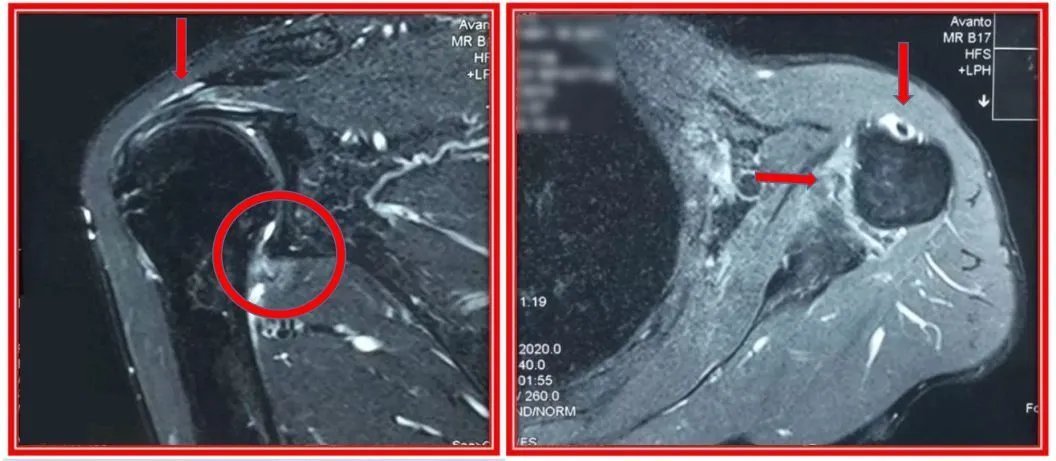

文章插图

上图为一例严重肩袖钙化性肌腱患者X光片,红色箭头所指为钙盐沉积